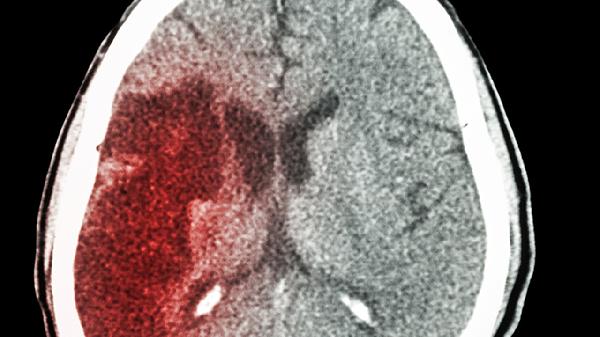

脑出血后能否同房需根据恢复情况判断,病情稳定且无不适症状时通常可以,若存在肢体功能障碍或血压控制不佳则不建议。

若患者仍存在明显肢体活动障碍、认知功能受损或血压波动较大,同房可能诱发再出血风险。部分患者服用抗凝药物期间,剧烈活动可能增加出血倾向。合并高血压、糖尿病等基础疾病未有效控制者,性兴奋可能导致血压骤升。此外,部分患者会出现性功能障碍或心理恐惧,强行同房可能加重焦虑情绪。

脑出血患者恢复同房前应进行专业评估,包括头部CT复查、血压监测及心功能检查。建议从温和的亲密接触开始逐步尝试,避免清晨或寒冷时段进行。日常需保持低盐低脂饮食,规律服用降压药物,保证充足睡眠。若出现异常出血、持续头痛或意识改变,须立即就医。